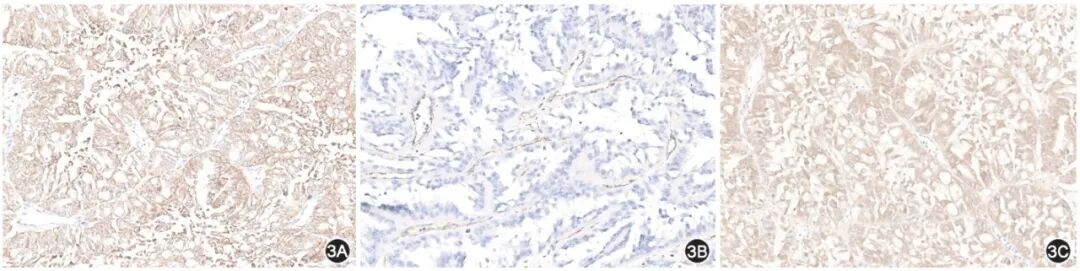

(二)免疫组化及FH检测

1.FH基因及蛋白缺陷:大多数FH-RCC可通过免疫组化方法检测到肿瘤细胞FH蛋白表达缺失(图3A),但少数患者FH蛋白表达阳性,单纯采用免疫组化检测FH诊断FH-RCC的灵敏度不高。FH突变是FH蛋白表达缺失或功能丧失的最常见原因(详见FH-RCC基因检测部分)。FH胚系突变是HLRCC的特异性基因改变,仅有FH体系突变则既往统一命名为FH-RCC[8-9]。由于FH胚系和体系突变或大片段缺失所致RCC具有相同的病理和生物学行为特征,因此即将发布的2022新版WHO病理分类中将胚系和体系FH突变的罕见肾细胞癌统一归类为FH-RCC。

2.2-琥珀酸-半胱氨酸[S-(2-succino)cysteine,2SC]:FH是三羧酸循环的关键代谢酶,其缺陷导致细胞内延胡索酸盐堆积,进而引发细胞内蛋白发生一种稳定的化学修饰:异常琥珀酸化,修饰后的蛋白可以通过2SC抗体进行检测。2SC在FH-RCC中阳性率为100%,阳性表现为弥漫性细胞核和细胞质强阳性(图3B),可用于FH-RCC的辅助诊断。但少部分肾透明细胞癌及乳头状肾细胞癌也可弱阳性表达2SC。

3.AKR1B10:FH缺陷可导致KEAP1-NRF2通路的异常[10-11],NRF2表达增加进一步促进AKR1B10表达[11]。研究结果显示,FH下调或表达缺失后AKR1B10明显升高[12]。AKR1B10免疫组化阳性表现为弥漫性细胞质和细胞核强阳性(图3C),诊断FH-RCC的灵敏度和特异度较高,可作为诊断FH-RCC的潜在标志物。

图3  (3A应与3B互换图片,请以正式版为准)延胡索酸水合酶缺陷型肾细胞癌免疫组化染色典型图片(×200):3A示延胡索酸水合酶在肿瘤细胞中表达缺失,3B示2-琥珀酸-半胱氨酸在肿瘤细胞中表达强阳性,3C示AKR1B10蛋白在肿瘤细胞中表达强阳性

【共识3】免疫组化检测FH蛋白是诊断FH-RCC的重要手段,但部分FH-RCC肿瘤细胞仍可表达FH蛋白。建议联合检测FH、2SC和AKR1B10,以提高FH-RCC的诊断准确率(70%)。在寻找FH蛋白缺陷的原因时,如基因检测未能检测到相应的FH突变时,建议结合临床病理学特征加做多重连接依赖性探针扩增(multiplex ligation-dependent probe amplification,MLPA)检测,判断是否存在FH大片段缺失(86%)。